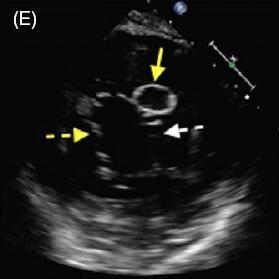

患者女,42 岁,以「急性视网膜动脉闭塞」病史就诊,既往无慢性疾病。经胸超声心动图检查发现二尖瓣后叶可见一囊状结构,可活动(图 A 和 B)。二维和实时三维经食管超声心动图检查显示一柔软的圆形结构附着于二尖瓣后叶,活动性良好(图 C ~ G)。主动脉弓、左心房、左心耳和左心室均正常。根据病变形态特征及超声表现,诊断为二尖瓣附瓣。其它影像学检查如 MRI、颈动脉多普勒超声均无异常。基于上述检查结果,考虑急性视网膜动脉闭塞为 AMVT 所致,建议外科手术切除二尖瓣附属组织,但是患者拒绝,选择随访观察。

图 C~F 二维经食管超声心动图显示一柔软的圆形结构附着于二尖瓣后叶,活动性良好